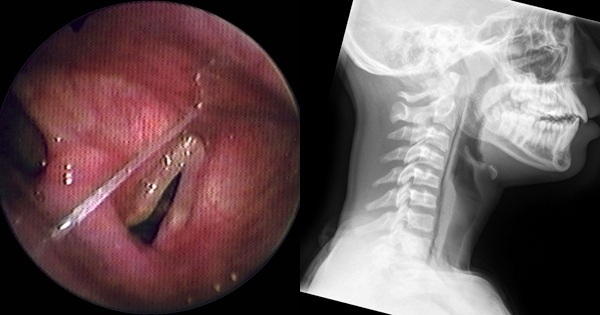

鱼肉营养鲜美,但刺太多,一不小心就会被卡住。很多人发现鱼刺卡在喉咙后,会强行吞嚥,其实这样的方法并不能解决问题。▼如果鱼刺比较坚硬,吞嚥的过程会对喉咙和食道…